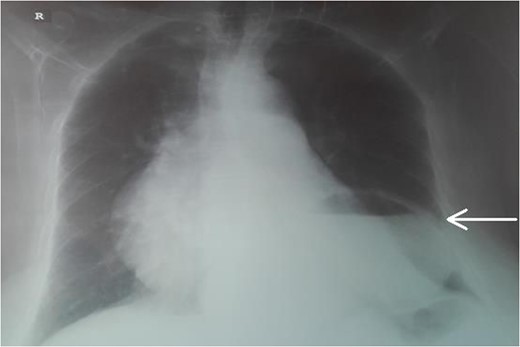

An 87-year-female patient was admitted to emergency department complaining about vomiting for the past 7 days with mild abdominal pain. The patient was hemodynamically stable, had sluggish bowel sounds and soft abdominal wall with mild tenderness. The patient also suffered from atrial fibrillation, heart failure, myelodysplastic syndrome, hiatus hernia and cholelithiasis. The findings of the laboratory tests were unremarkable. Plain chest and abdominal radiograms revealed hiatus hernia with gastric dilation (Fig. 1), a few air-fluid levels and pneumobilia, with delineation of extrahepatic and intrahepatic bile ducts by air (Fig. 2). A nasogastric tube was inserted, which drained biliary content. An abdominal computed tomography (CT) scan revealed the presence of air in the intrahepatic bile ducts, free air and leakage of oral contrast agent in the hepatic hilum and subhepatic space and an impacted gallstone in the third portion of the duodenum (Figs 3 and 4). The diagnosis of cholecystoenteric fistula and proximal gallstone ileus was set.

Abdominal CT scan (axial plane). The arrow shows the impacted gallstone.